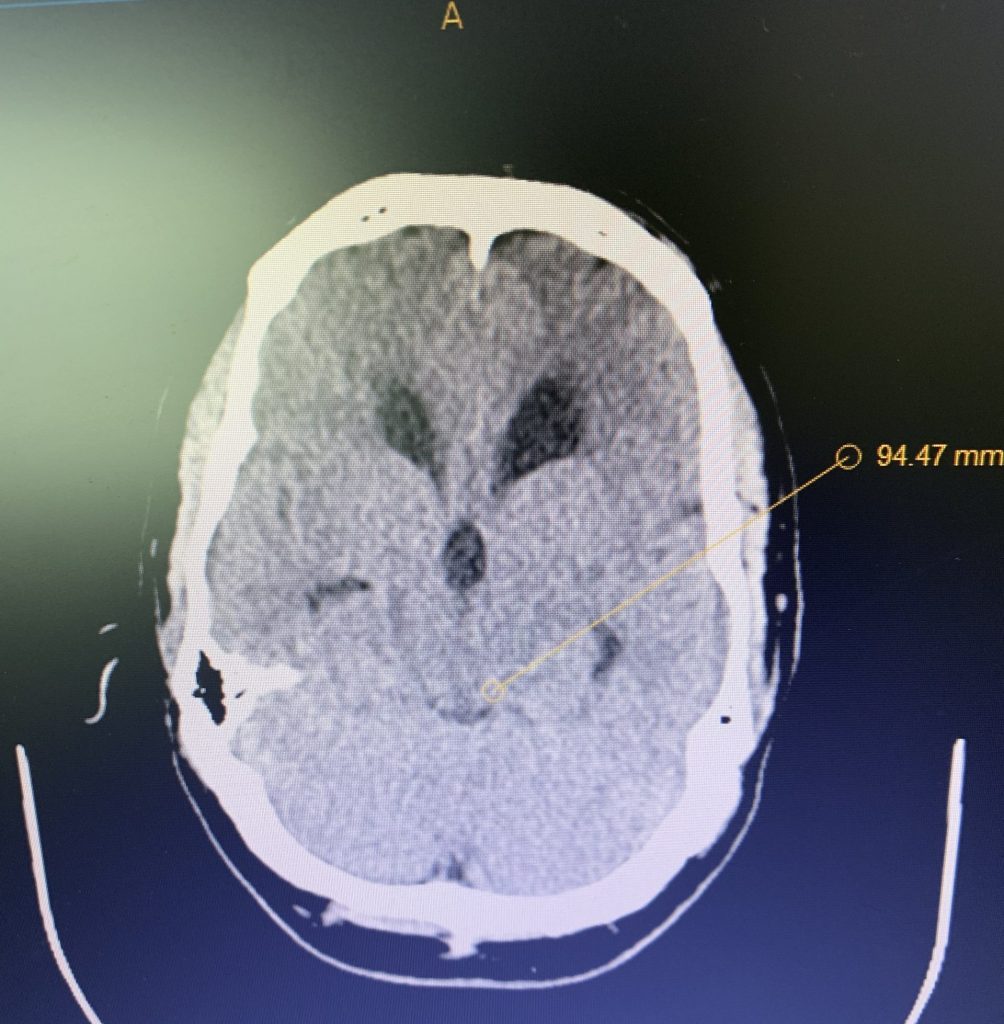

The patient is a 59-year-old gentleman who is otherwise healthy, but states that he had a traumatic head injury several months prior for which he was […]